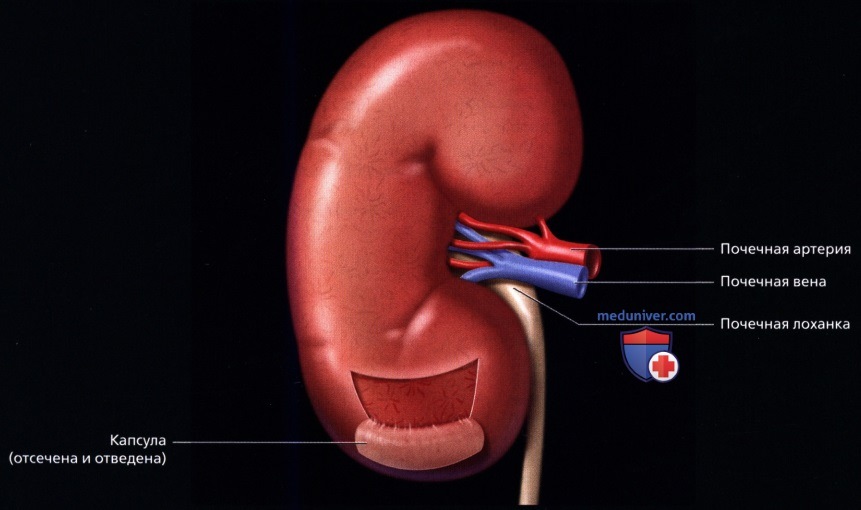

а) Анатомия почек:

2. Топографическая анатомия почки:

3. Внутренняя структура:

• Почки можно рассматривать как полый орган, просвет которого занят жировой тканью, почечной лоханкой, чашечками, сосудами и нервами

• Ворота почки: сюда подходят артерия и вена и выходит мочеточник

• Почечная лоханка: расширение верхнего конца мочеточника в виде воронки:

о Собирает мочу от больших чашечек (2 или 3), каждая из которых в свою очередь собирает мочу от малых чашечек (2-4)

• Почечный сосочек: точечная верхушка почечной пирамиды, содержащей собирательные трубочки, выделяющие мочу

о Каждый сосочек открывается в малую чашечку

• Корковое вещество почки: периферическая часть, содержит почечные (клубочки, сосуды), проксимальные части собирательных трубочек и петли Генле

• Мозговое вещество почки: внутренняя часть, содержит почечные пирамиды, дистальные части собирательных трубочек и петли Генле